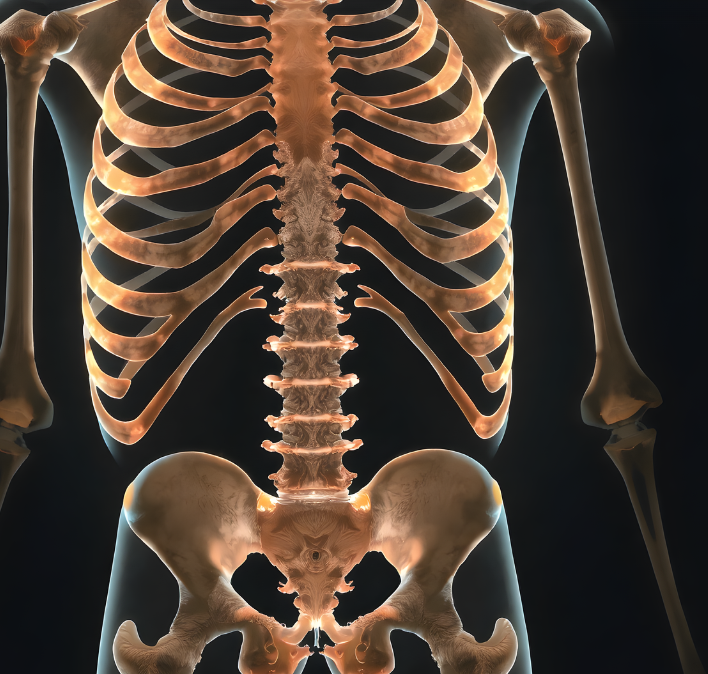

🦴 골다공증이란? 왜 위험할까요?

골다공증은 뼈의 밀도가 감소하고 구조가 약해져 쉽게 골절될 위험이 높은 질환입니다.

특히 나이가 들면서 뼈가 약해지는 자연스러운 과정이지만, 일부 요인에 의해 더 빠르게 진행될 수 있습니다.

- 척추뼈, 손목, 고관절 골절 위험 증가

- 심한 경우 허리뼈가 무너져 압박골절이 생길 수도 있음